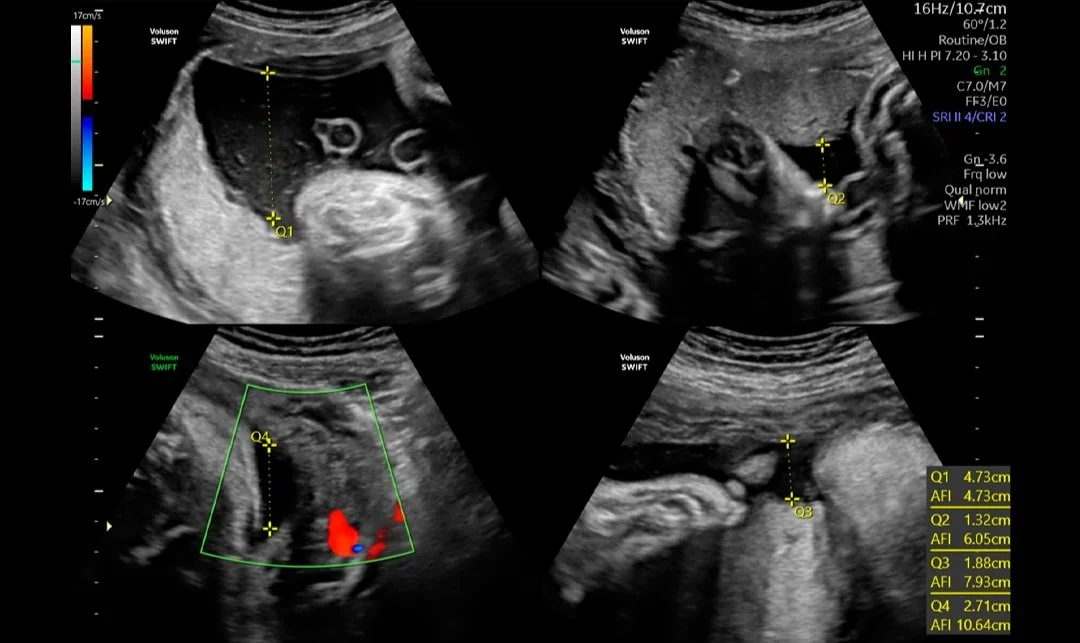

Diagnóstico pormenorizado

El proceso de parto está lleno de emoción, expectativas y, a veces, incertidumbre. Con imágenes extraordinarias y seguimiento innovador de la evolución del parto, Voluson SWIFT puede ayudarlo a controlar la progresión del parto, así como el bienestar tanto del bebé como de la madre, lo que lo ayuda a tomar decisiones clínicas más informadas.